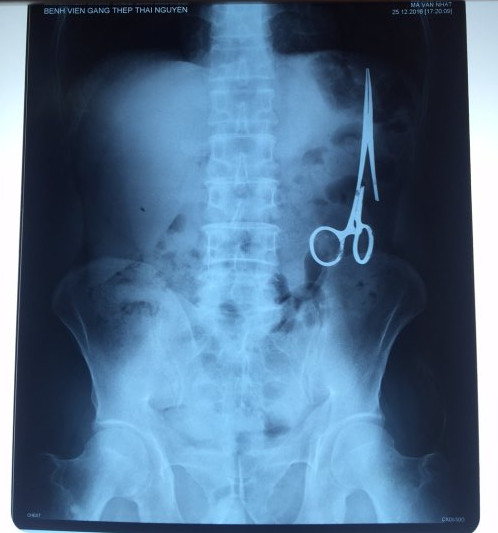

遺留在病人腹中的剪刀

據(jù)越南青年報(bào)1月2日?qǐng)?bào)道,在越南首都河內(nèi)醫(yī)療專家的幫助下,越南東北部的太原省(Thai Nguyen)鑄鋼醫(yī)院的醫(yī)生日前從54歲患者M(jìn).V.N腹中取出一把醫(yī)用剪刀。這把剪刀是此前曾為M.V.N手術(shù)的醫(yī)生遺留的,已經(jīng)在其腹中待了18年時(shí)間。

醫(yī)務(wù)人員表示,這把剪刀遺留在病人腹部左側(cè),與結(jié)腸緊挨著。剪刀的把手已經(jīng)生銹,部分器官也已經(jīng)與剪刀粘連起來(lái)。但在過(guò)去多年中,M.V.N沒(méi)有任何不適感覺(jué),也從未因?yàn)榱粼诟怪械募舻兑l(fā)的相關(guān)問(wèn)題去看過(guò)醫(yī)生。直到2016年12月,M.V.N因?yàn)樵庥隽艘粓?chǎng)車禍,才到鑄鋼醫(yī)院進(jìn)行身體檢查。

超聲波檢查顯示,M.V.N的腸子中有個(gè)奇怪物體,看起來(lái)就像醫(yī)用剪刀。M.V.N證實(shí),他曾于1998年6月份在北江省綜合醫(yī)院接受手術(shù),在此后也從未進(jìn)行過(guò)任何手術(shù)。近來(lái),他感到腹部有些疼痛,并試圖通過(guò)服用藥物治療。12月27日,M.V.N回到北江省綜合醫(yī)院再次進(jìn)行超聲波檢查,顯示其腹部的確存在怪異物體。